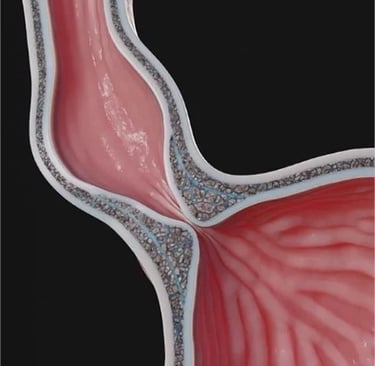

A acalasia é um distúrbio do esôfago que dificulta a passagem dos alimentos para o estômago, levando a engasgo, sensação de comida “parando” e perda de peso. No Brasil, além das causas sem origem definida, a Doença de Chagas é uma causa importante. O tipo de tratamento a ser realizado pode variar de acordo com a gravidade do problema, mas a cirurgia minimamente invasiva tem um papel muito importante para o tratamento desses pacientes.

A Doença do Refluxo Gastroesofágico causa sintomas como azia, queimação e regurgitação e nem sempre precisa ser controlada apenas com medicamentos por toda a vida. Em casos selecionados, a cirurgia de fundoplicatura (técnica que reforça a “válvula” entre esôfago e estômago) pode proporcionar alívio duradouro dos sintomas e reduzir a dependência de remédios. A decisão é tomada após uma avaliação cuidadosa, que pode incluir endoscopia e exames específicos. Agende uma consulta para entender se essa abordagem é adequada ao seu caso.